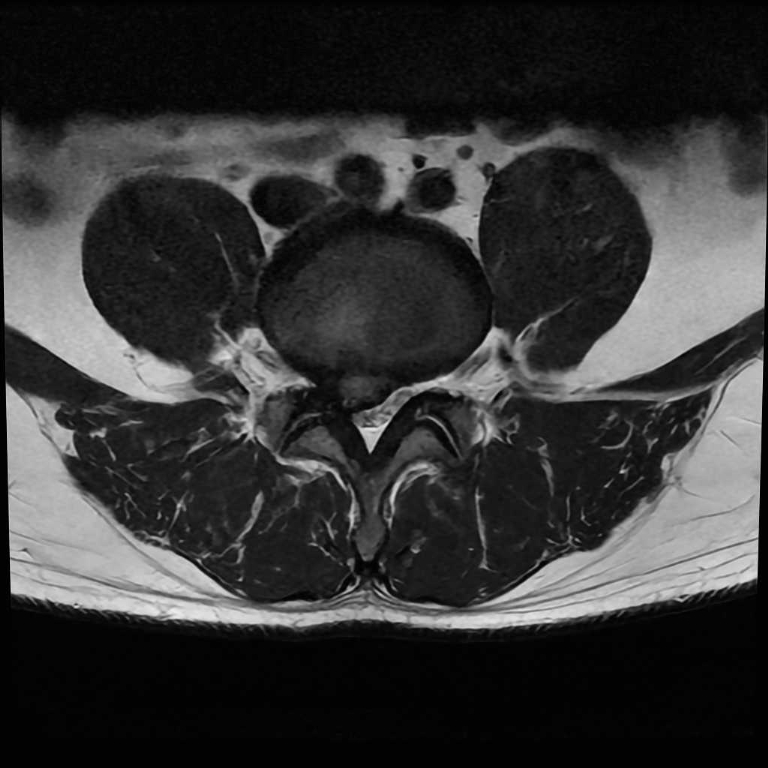

男性器領域

前立腺

前立腺肥大